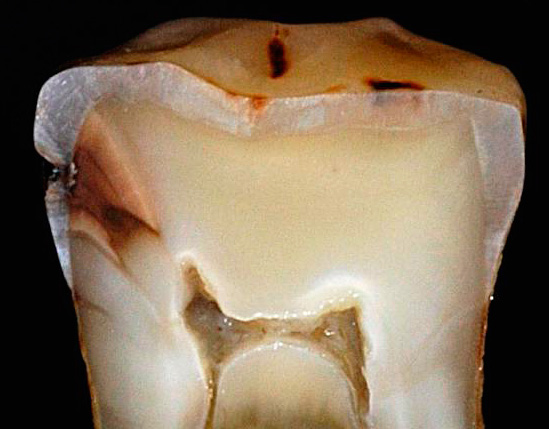

In alcuni casi, anche la carie profonda, che ha un decorso cronico, passa con sintomi minori, per non parlare delle fasi iniziali del processo carioso, quando la malattia può essere trattata senza riempimento. Ciò è in parte dovuto alla formazione della dentina sostitutiva, una reazione adattativa di un dente vivente all'apparizione di un fuoco irritante infettivo, quando si formano tessuti secondari che proteggono il nervo da agenti esterni e irritanti.

- La carie media cronica è caratterizzata da un'ampia cavità che colpisce la dentina. In questo corso, la cavità non ha ammorbidito la dentina, ma solo pigmentata dentina cariata. Il fondo è denso con lievi sporgenze e rugosità, che indica un processo lento nella fase di compensazione a causa della sostituzione della dentina.

- La carie cronica profonda differisce dalla media solo per la profondità della cavità. Inoltre non ha bordi a smalto sporgenti, generalmente ben lucidati.

In generale, la carie cronica si verifica per gli stessi motivi tipici della carie in generale, a causa dell'attività dei batteri che trasformano i residui di carboidrati nella bocca in acidi organici. Questi acidi influenzano regolarmente lo smalto dei denti e in un modo o nell'altro portano alla sua distruzione. Quindi la dentina che giace sotto lo smalto viene distrutta.